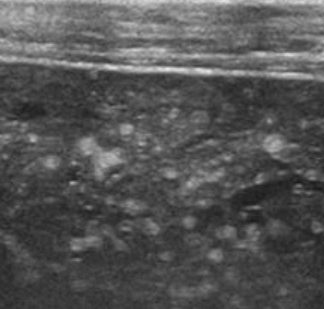

- 간문부와 직경이 큰 문맥관 주변에 호발 한다.

- portal vein을 따라 산재된 낭성병변 (포도송이 모양)

- 원인은 주로 간경변, 알코올성 간질환이 심한 환자에서 발견된다.

담관주변 낭종 (Peribiliary cyst) 췌담관 이상 유합 (Anomalous PancreaticoBiliary ductal Union , APBU)